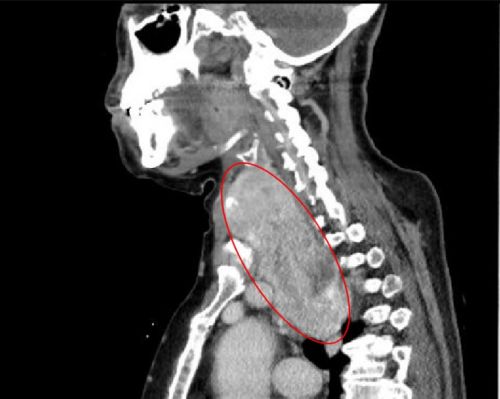

ct显示:左侧甲状腺肿瘤有成人拳头大小。

ct显示:巨大的右侧甲状腺肿瘤从颈部延伸至胸腔。

双侧巨大甲状腺肿瘤将气道挤压成一条细缝。

完善相关检查发现,老人左侧颈部有一个成人拳头大小的肿块,右侧颈部肿块更大、且向胸腔内生长。耳鼻咽喉头颈外科、呼吸内科、心血管内科、心胸外科、放射科、麻醉科、手术室等多学科专家讨论后一致认为,患者高龄且有冠心病等基础疾病,而且肿瘤巨大,手术难度和风险都很大。

据主刀的肖旭平主任医师介绍,两个巨大的肿块“左右夹击”,导致颈段气管被压成了一条细缝,造成呼吸困难,术中极易出现窒息,给麻醉插管带来很大的风险。手术团队在精细操作的同时,巧妙利用肌肉间隙入路,既顺利切除巨大肿瘤,又减轻了创伤、缩短住院时间、有助于快速康复。